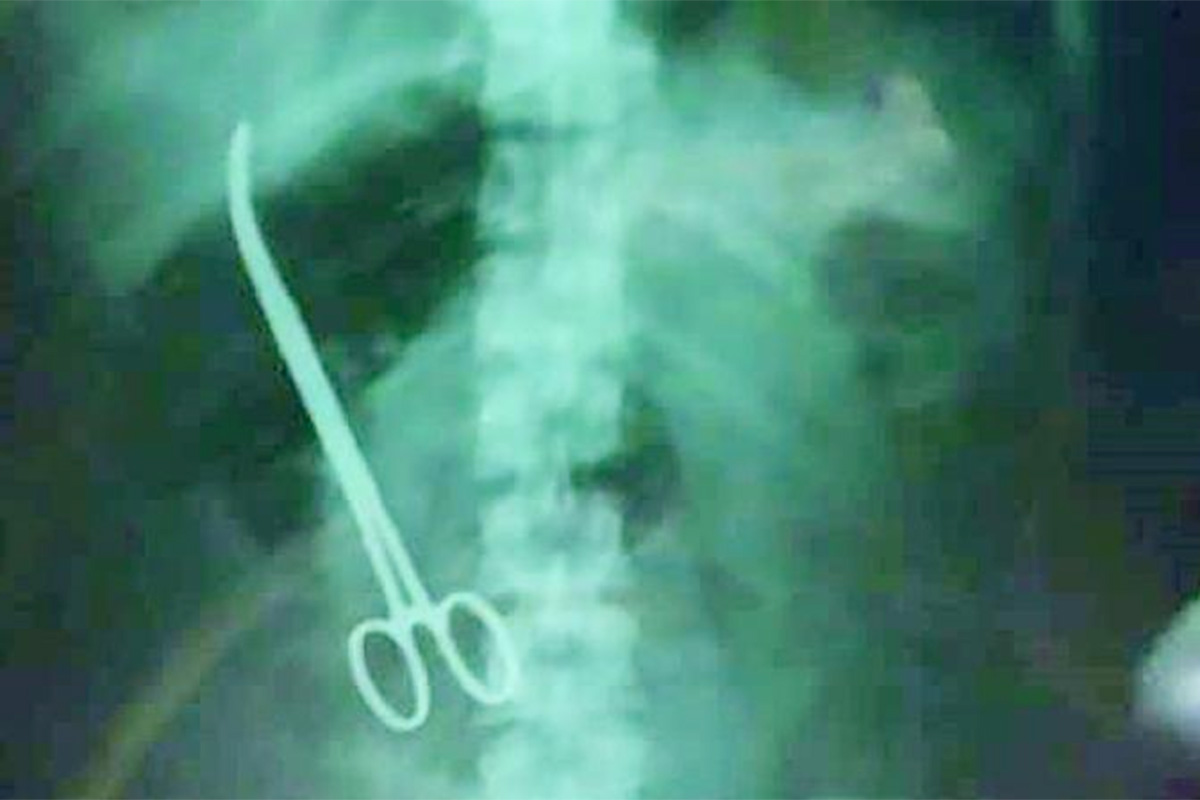

നവംബര് രണ്ടിന്് ഓപ്പറേഷന് നടന്നു. പന്ത്രണ്ടിന് ഡിസ്ചാര്ജും ചെയ്തു. പിന്നീട് കാര്യമായ പ്രശ്നങ്ങളൊന്നുമില്ലാതെ ദിവസങ്ങള് കടന്നുപോയി. എന്നാല് 2019 ഫെബ്രുവരി എട്ടിന് കഠിനമായ വേദനയും ഛര്ദ്ദിയും മൂലം മഹേശ്വരി വീണ്ടും ആശുപത്രിയിലെത്തി. എക്സറേ പരിശോധനയിലാണ് വയറിനുള്ളില് കത്രിക കണ്ടെത്തിയത്. തുടര്ന്ന് അടിയന്തിര ശസ്ത്രക്രിയ നടത്തുകയായിരുന്നു. റേഡിയോളജി ഡിപ്പാര്ട്ട്മെന്റ് ഇക്കാര്യം മറച്ചുവയ്ക്കാന് ശ്രമിക്കുകയായിരുന്നുവെന്ന് മഹേശ്വരിയുടെ ഭര്ത്താവ് കുറ്റപ്പെടുത്തി. കത്രിക മറന്നുപോയത്് നിര്ഭാഗ്യകരമായ സംഭവമാണെന്ന് ഹോസ്പിറ്റല് ഡയറക്ടര് ഡോ. കെ മനോഹര് പ്രതികരിച്ചു.